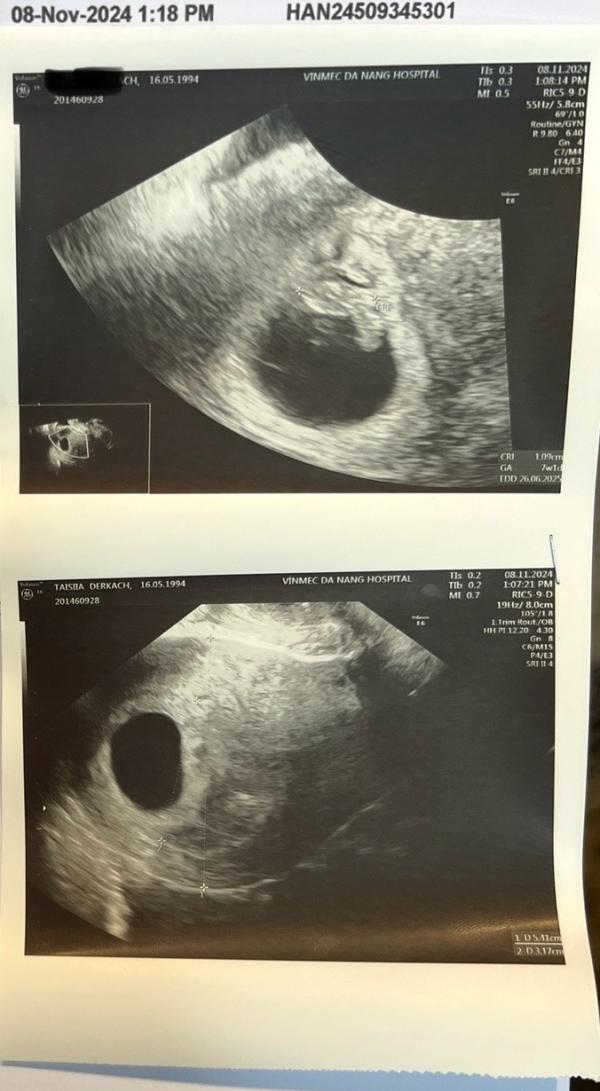

Первое узи во Вьетнаме прошло хорошо.

Впечатления от больницы приятные. Это международный госпиталь Vinmec. Прием был платный. Впечатлило, что на узи выдают одноразовую юбку (или футболку, если смотрят верхнюю часть) Это как-то уважительно к пациенту. В РФ даже в платных я помню, как обычно бегаешь с голой жопой 😂 может меня подводит память и у вас было по-другому? В принципе стандартно спросили первый день последнего цикла, измерили рост, вес, давление, сердцебиение мое. Уточнили про аллергии. Дальше само узи и консультация по итогу. Цена сего мероприятия была 1,5 млн или 5.800 руб.

Срок беременности поставили 7 недель и 1 день. Я думала, что там неделек пять эмбриональных, но оказалось, что нет)

КТР 1,09

Пульс 155 ударов в минуту

Следующий визит - первый скрининг, ориентировочно между 13 и 17 декабря)